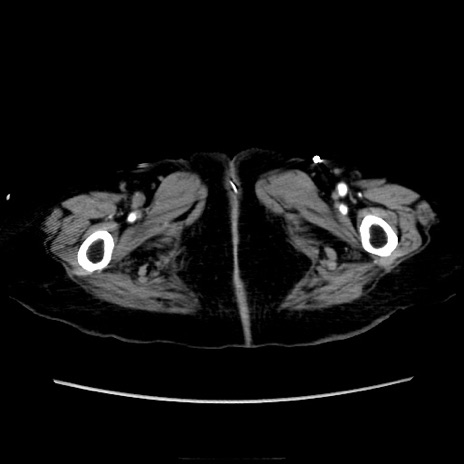

症例40(横断像)

【症例】90歳代女性

【主訴】腹痛・嘔吐

【現病歴】 食欲低下、嘔吐があり昨日他院受診。肺炎と診断され入院となる。入院後より腹部全体に圧痛あり。胃管留置され経過みていたが、症状持続するため、

当院転院となる。

【既往歴】胸椎圧迫骨折、胆石症

【身体所見】腹部:中央に激痛あり、圧痛あり、反跳痛不明

【データ】WBC 17100、CRP 18.82